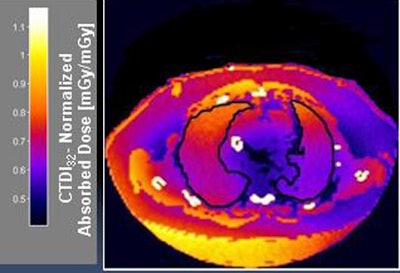

Each dataset was then "voxelized" to create a patient-specific virtual phantom. Each voxel was assigned a material type based on a priori global HU classification intervals per the International Commission on Radiation Units and Measurements Report 44.

Two readers manually segmented skin, lungs, breast, stomach, liver, and esophagus regions from dose maps, then determined the effective dose.